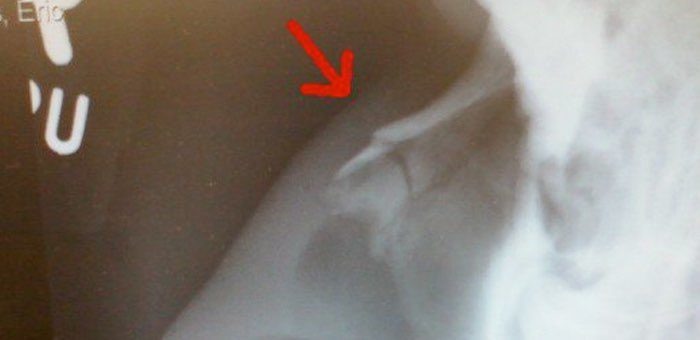

За несколько часов до наступления Нового года в приемный покой Республиканской больницы обратилась 47-летняя горожанка, у которой был диагностирован перелом носа. Женщина призналась, что ее ударил муж. Предварительно установлено, что накануне Нового года супруги находились в гостях у знакомых. Затем мужчина стал собираться домой, а женщина заявила, что хочет еще погостить. Горожанин разозлился и ушел в одиночестве. Когда женщина вернулась домой, муж начал высказать претензии из-за ее поведения, вспыхнула ссора, и мужчина ударил жену в лицо кулаком. Возбуждено уголовное дело по признакам преступления, предусмотренного ч. 1 ст. 112 УК РФ (умышленное причинение средней тяжести вреда здоровью), сообщает пресс-служба МВД по Республике Алтай.

За несколько часов до наступления Нового года в приемный покой Республиканской больницы обратилась 47-летняя горожанка, у которой был диагностирован перелом носа. Женщина призналась, что ее ударил муж.